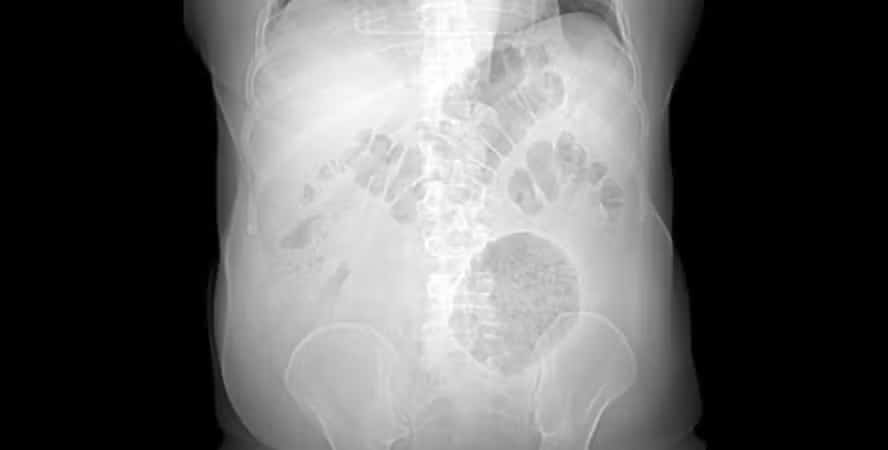

Médicos relataram uma formação inflamatória de 13 x 12 x 10cm na região abdominal. Em média, este tipo de inflamação tem entre 4 e 9cm de diâmetro. Segundo a SMS, o paciente é um homem de 62 anos que chegou na emergência do hospital com dores abdominais e perda de peso, alguns dos sintomas mais comuns de divertículo. Os problemas persistiam há pelo menos dois meses. Ele foi operado no Salgado Filho e está plenamente recuperado.

A SMS explicou que o exame clínico realizado na emergência indicou a presença de uma massa flácida, palpável e dolorosa no flanco esquerdo do abdome. Ao ver o resultado da tomografia computadorizada, Leonardo Fiuza ficou incrédulo com o tamanho da inflamação.

Uma semana depois, a cirurgia de laparotomia exploradora confirmou a existência de massa inflamatória na parede abdominal e no cólon sigmoide, que fica na porção final do intestino grosso. Os médicos relataram que o paciente teve uma recuperação tranquila e recebeu alta quatro dias depois.